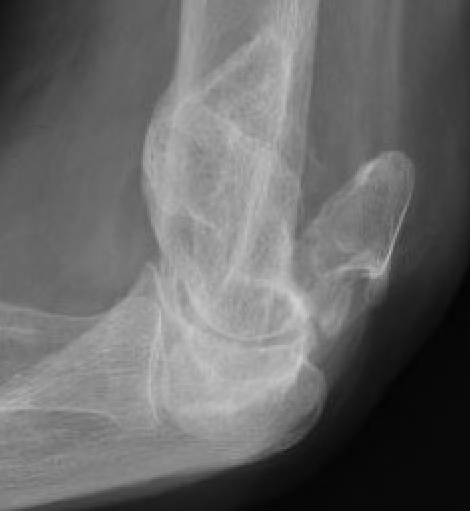

Olecranon Osteotomy

Indication

Complex intra-articular fractures

Technique

AO foundation surgery reference Chevron osteotomy

Chevron

- distally based V shaped

- through bare area of olecranon / smallest width of greater sigmoid notch

- 3 cm from tip

Fixation

- TBW v plate v intramedullary screw

Results

- systematic review of olecranon osteotomy and paratricipital approach

- longer operative time and higher incidence of infection with osteotomy

- no difference in outcome / ROM / hetertopic ossification / ulnar nerve injury

Coles et al J Orthop Trauma 2006

- 67 intra-articular fractures treated with olecranon osteotomy

- no nonunions